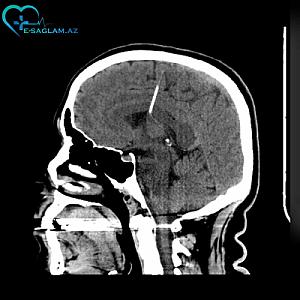

Azərbaycanda qadının beynində iynə aşkarlandı -

Azərbaycanda qadının beynində iynə aşkarlandı - İllərdir belə yaşayıb + FOTOLAR